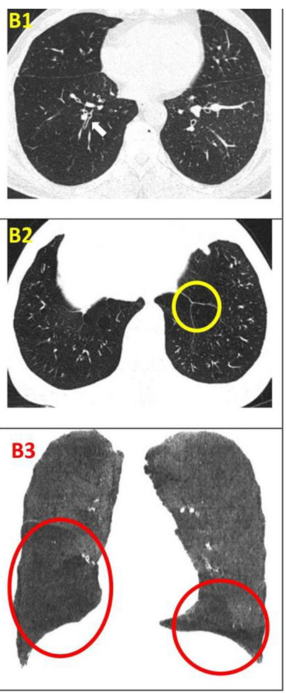

影像學(xué)檢查:對于患者 #2902,定量分析顯示基線時總體肺氣腫面積比為 12.75%,移植后 24 周降至 10.02%。在患者 #8009 中,肺氣腫面積比值從基線的 10.85% 下降到移植后 12 周的 9.08%。CT 圖像的三維可視化顯示,肺氣腫的減輕在下葉比在上葉更明顯。

影像學(xué)檢查:隨訪12個月時,定量胸部CT掃描示患者吸入總肺容積略有增加,肺氣腫指數(shù)無明顯變化。支氣管壁厚度(WT)的變化以WT、壁面積(WA)及WA百分比(%WA)的減少,以及支氣管內(nèi)徑(ID)和管腔面積(LA)的增大來評估。

干細(xì)胞治療一年后,雙肺RB1和RB10的WT均減少,LA增加(粗體指數(shù))。